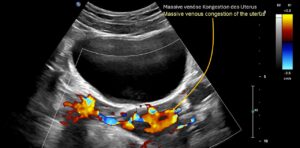

- Es bestand eine vollständige Kompression der Vena iliaca communis sinistra, die zu einer massiven Stauung der Beckenorgane geführt hatte

- eine Kollateralisation von 50% des gestauten Blutvolumens zum Spinalkanal über die Vena lumbalis ascendens links